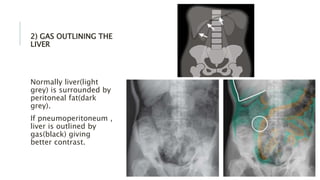

2) GAS OUTLINING THE

LIVER

Normally liver(light

grey) is surrounded by

peritoneal fat(dark

grey).

If pneumoperitoneum ,

liver is outlined by

gas(black) giving

better contrast.